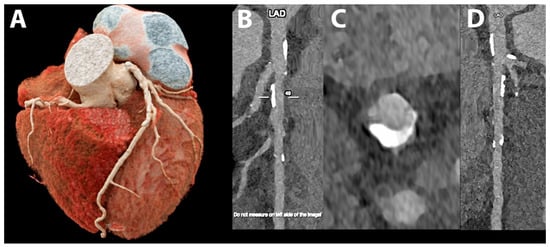

5.4. Coronary Artery Stenting

- Boccalini, S.; Si-Mohamed, S.A.; Lacombe, H.; Diaw, A.; Varasteh, M.; Rodesch, P.A.; Villien, M.; Sigovan, M.; Dessouky, R.; Coulon, P.; et al. First In-Human Results of Computed Tomography Angiography for Coronary Stent Assessment With a Spectral Photon Counting Computed Tomography. Investig. Radiol. 2022, 57, 212–221. [Google Scholar] [CrossRef] [PubMed]